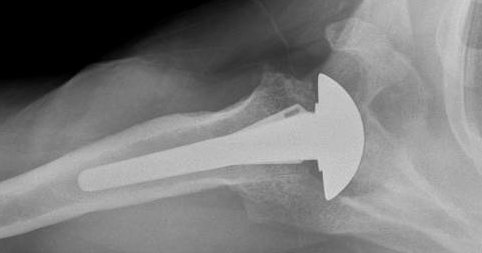

He elected a ream and run procedure to avoid the possibility of plastic glenoid failure.

His postoperative x-rays are shown here